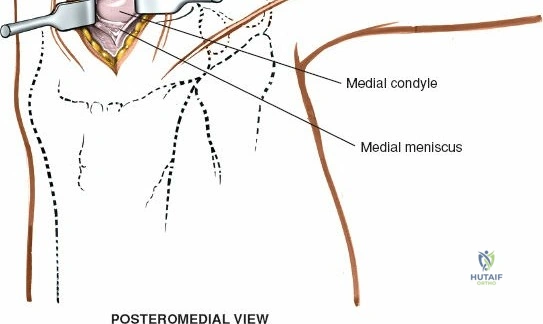

- Posteromedial Portal: An accessory portal, located posterior to the medial collateral ligament (MCL) at the level of the joint line, can be useful for visualization and instrumentation of complex posterior horn tears, particularly those extending into the meniscocapsular junction.

Open Medial Meniscectomy – The Specific Approach

The open medial meniscectomy, once the standard, is now reserved for scenarios where arthroscopy is unavailable, technically infeasible (e.g., severe arthrofibrosis, large foreign bodies, or specific revision surgeries), or for very large, difficult-to-manage loose bodies. The seed content heavily focuses on this approach.

- Landmarks: Palpate the medial joint line, medial epicondyle of the femur, and medial tibial plateau. The saphenous vein and nerve courses superficial and posterior to the medial femoral condyle, requiring careful attention.

Exposure of the Meniscus:

- To improve visualization, the knee is brought into hyperflexion (as per seed content, "beyond a right angle"). This maneuver, combined with external rotation of the tibia and a valgus stress applied to the knee, widens the medial compartment. This allows for improved access to the posterior horn of the medial meniscus.